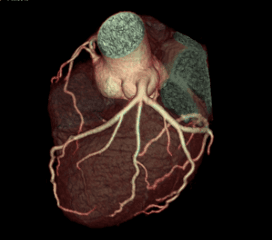

Coronary Angiogram

A CT Coronary Angiogram is a non-invasive imaging test that uses a CT scanner, and contrast dye to create detailed 3D pictures of your heart's arteries, revealing plaque, blockages, or narrowing (stenosis) that can cause heart problems like chest pain.

3D Vessel Analysis